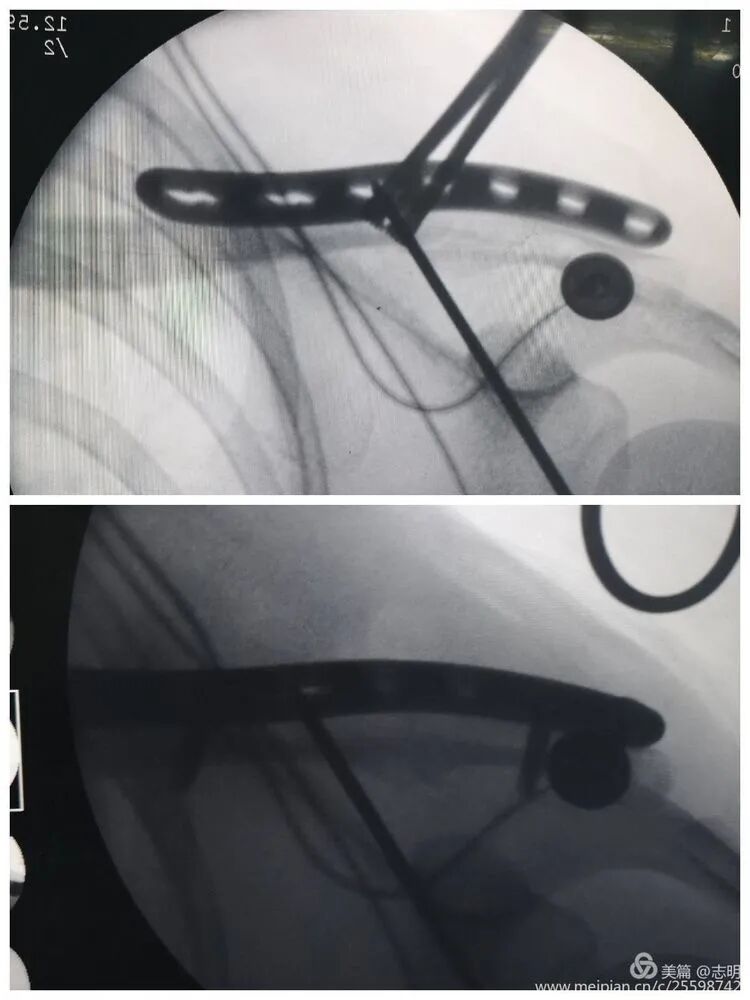

(Image depicting the insertion of a plate through a small incision). -

(Fluoroscopic image confirming proper plate positioning). -

(Another fluoroscopic view illustrating the plate's final position).

(Image showing percutaneous drilling through a guide). -

(Fluoroscopic image depicting screw insertion).